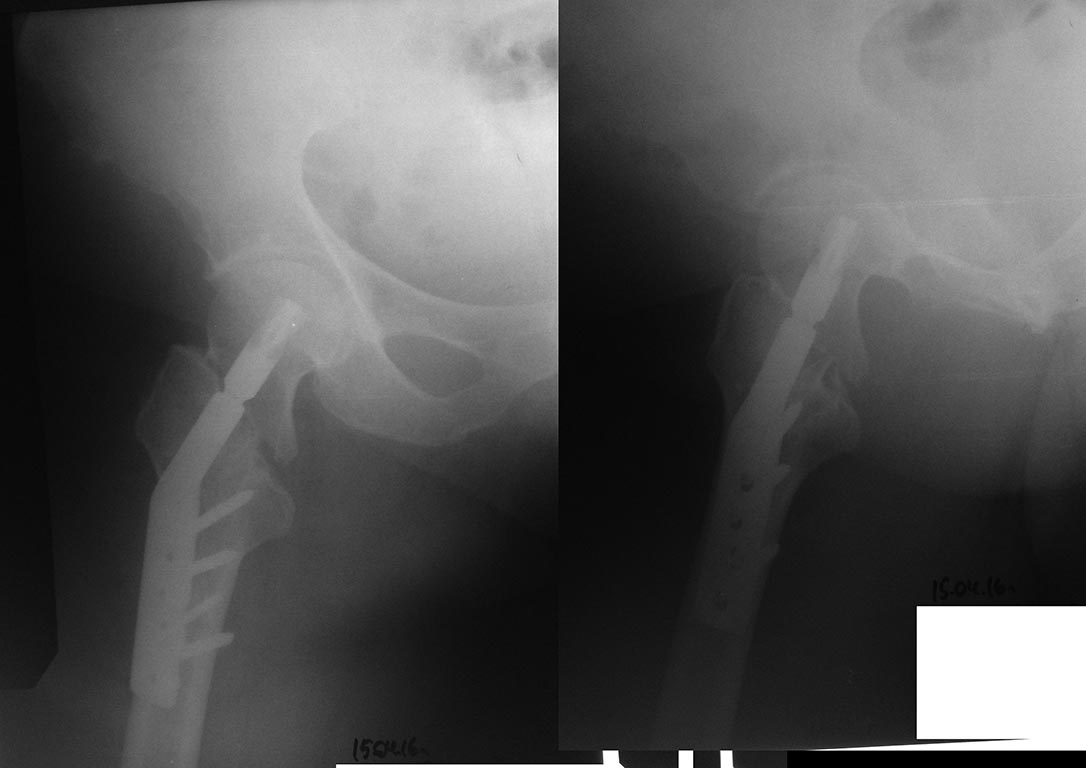

[Ortho] Миграция DHSA при лечение перелома проксимального отдела бедра

Снимки